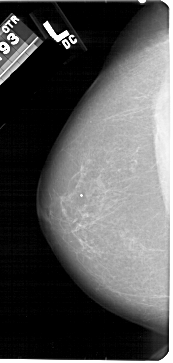

A_1428_1.LEFT_MLO

LEFT_MLO LINES 5491 PIXELS_PER_LINE 3001 BITS_PER_PIXEL 12 RESOLUTION 43.5 NON_OVERLAY